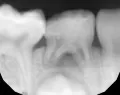

У нашей 5-летней дочери на нижней челюсти в районе центральных резцов с внутренней стороны видно, видимо, прорезывание постоянных резцов, небольшая припухлость. Резцы немного шатаются.

Нормально ли это? Я думал, что режущий край должен упереться в корень молочного и его вытолкнуть. А режущий край постоянного резца отстает во внутрь на несколько миллиметров.

В идеале они должны, как Вы выразились, вытолкнуть молочные зубы и встать на их место, но все не так просто, как кажется. Необходимо обратится к ортодонту, скорее всего придется удалить молочные зубы, чтобы освободить место для правильного прорезывания зубов.